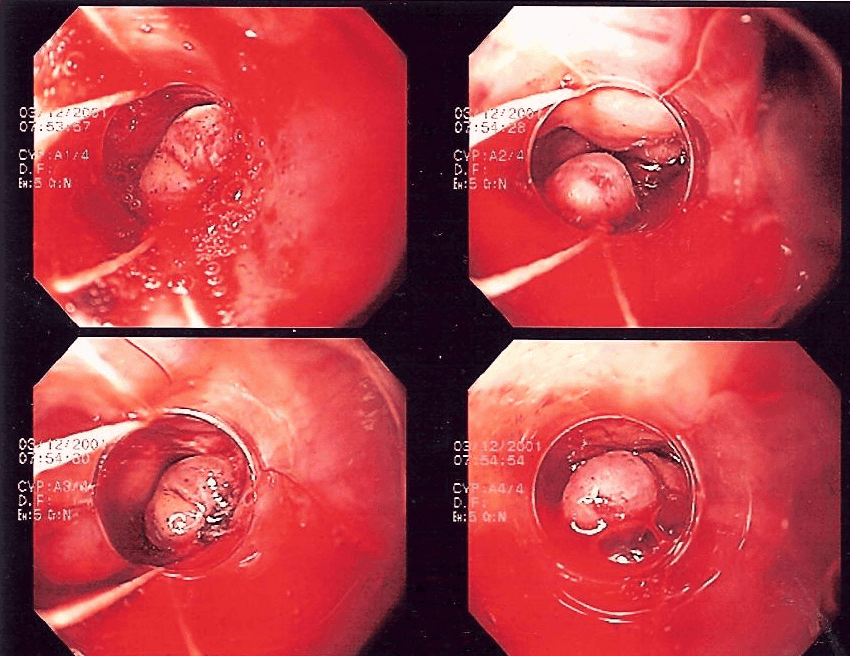

Image - Band ligation of oesophageal varices

Creative commons source by Samir [CC BY-SA 4.0 (https://creativecommons.org/licenses/by-sa/4.0)]

Patients present with large volumes of bright red haematemesis. They will also likely be pale and clammy. Upper GI bleeds can cause large volumes of blood to be lost. Therefore, management focuses on fluid/blood replacement, and finding and then stopping the source of bleeding, often using endoscopy. If the cause is oesophageal varices this is usually done by band ligation or a Transjugular Intrahepatic Portosystemic Shunt (TIPS). Terlipressin may also be used to reduce portal venous pressure. If the cause is peptic ulceration, proton pump inhibitors (PPIs) are used alongside endoscopic therapy, with surgical intervention reserved for cases where bleeding cannot be controlled.